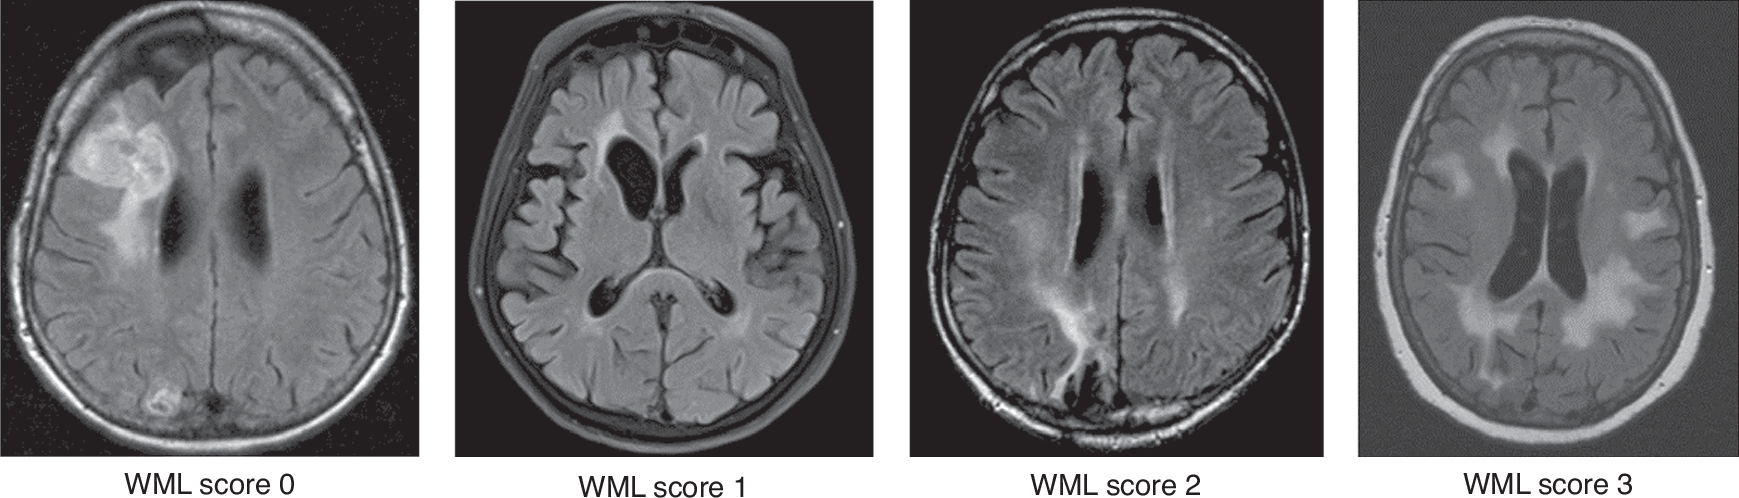

Fig. 1: Exemplary MRI scans scored by the modified Fazekas score (mFS) from score 0 to 3 for the overall white matter lesion (WML) burden.

All exemplary scans are from PCNSL patients. The assessment did not include specific lesions, such as tumor infiltration, post-therapeutic, or post-ischemic gliosis with surrounding edema.